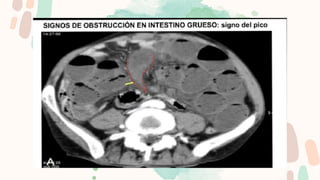

Los puntos más importantes son detectar el punto de transición, determinar la causa y

descartar la presencia de complicaciones.

Para facilitar la búsqueda del PT se emplean dos signos:

El “signo del pico”, dado que el punto de cambio de calibre simula un pico.

El “signo de las heces”, dado que debido a la obstrucción en el PT las heces se acumulan

proximalmente a este dando la típica imagen de patrón en miga de pan.